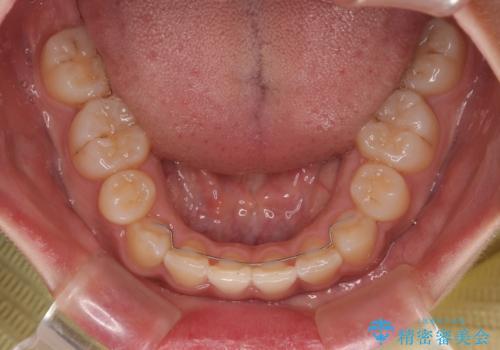

デコボコと捻れて前に飛び出した歯列 抜歯矯正でスッキリした口元に

- 前歯のデコボコと口元の突出感を気にして来院された患者様です。

非抜歯矯正ではデコボコを解消することでより口元が突出してしまうため、上下左右の小臼歯4本の抜歯を行い、ワイヤー装置による矯正治療を行うこととしました。

上顎小臼歯の歯根が左右ともに大きく曲がっており、スペースクローズに時間がかかってしまいました。